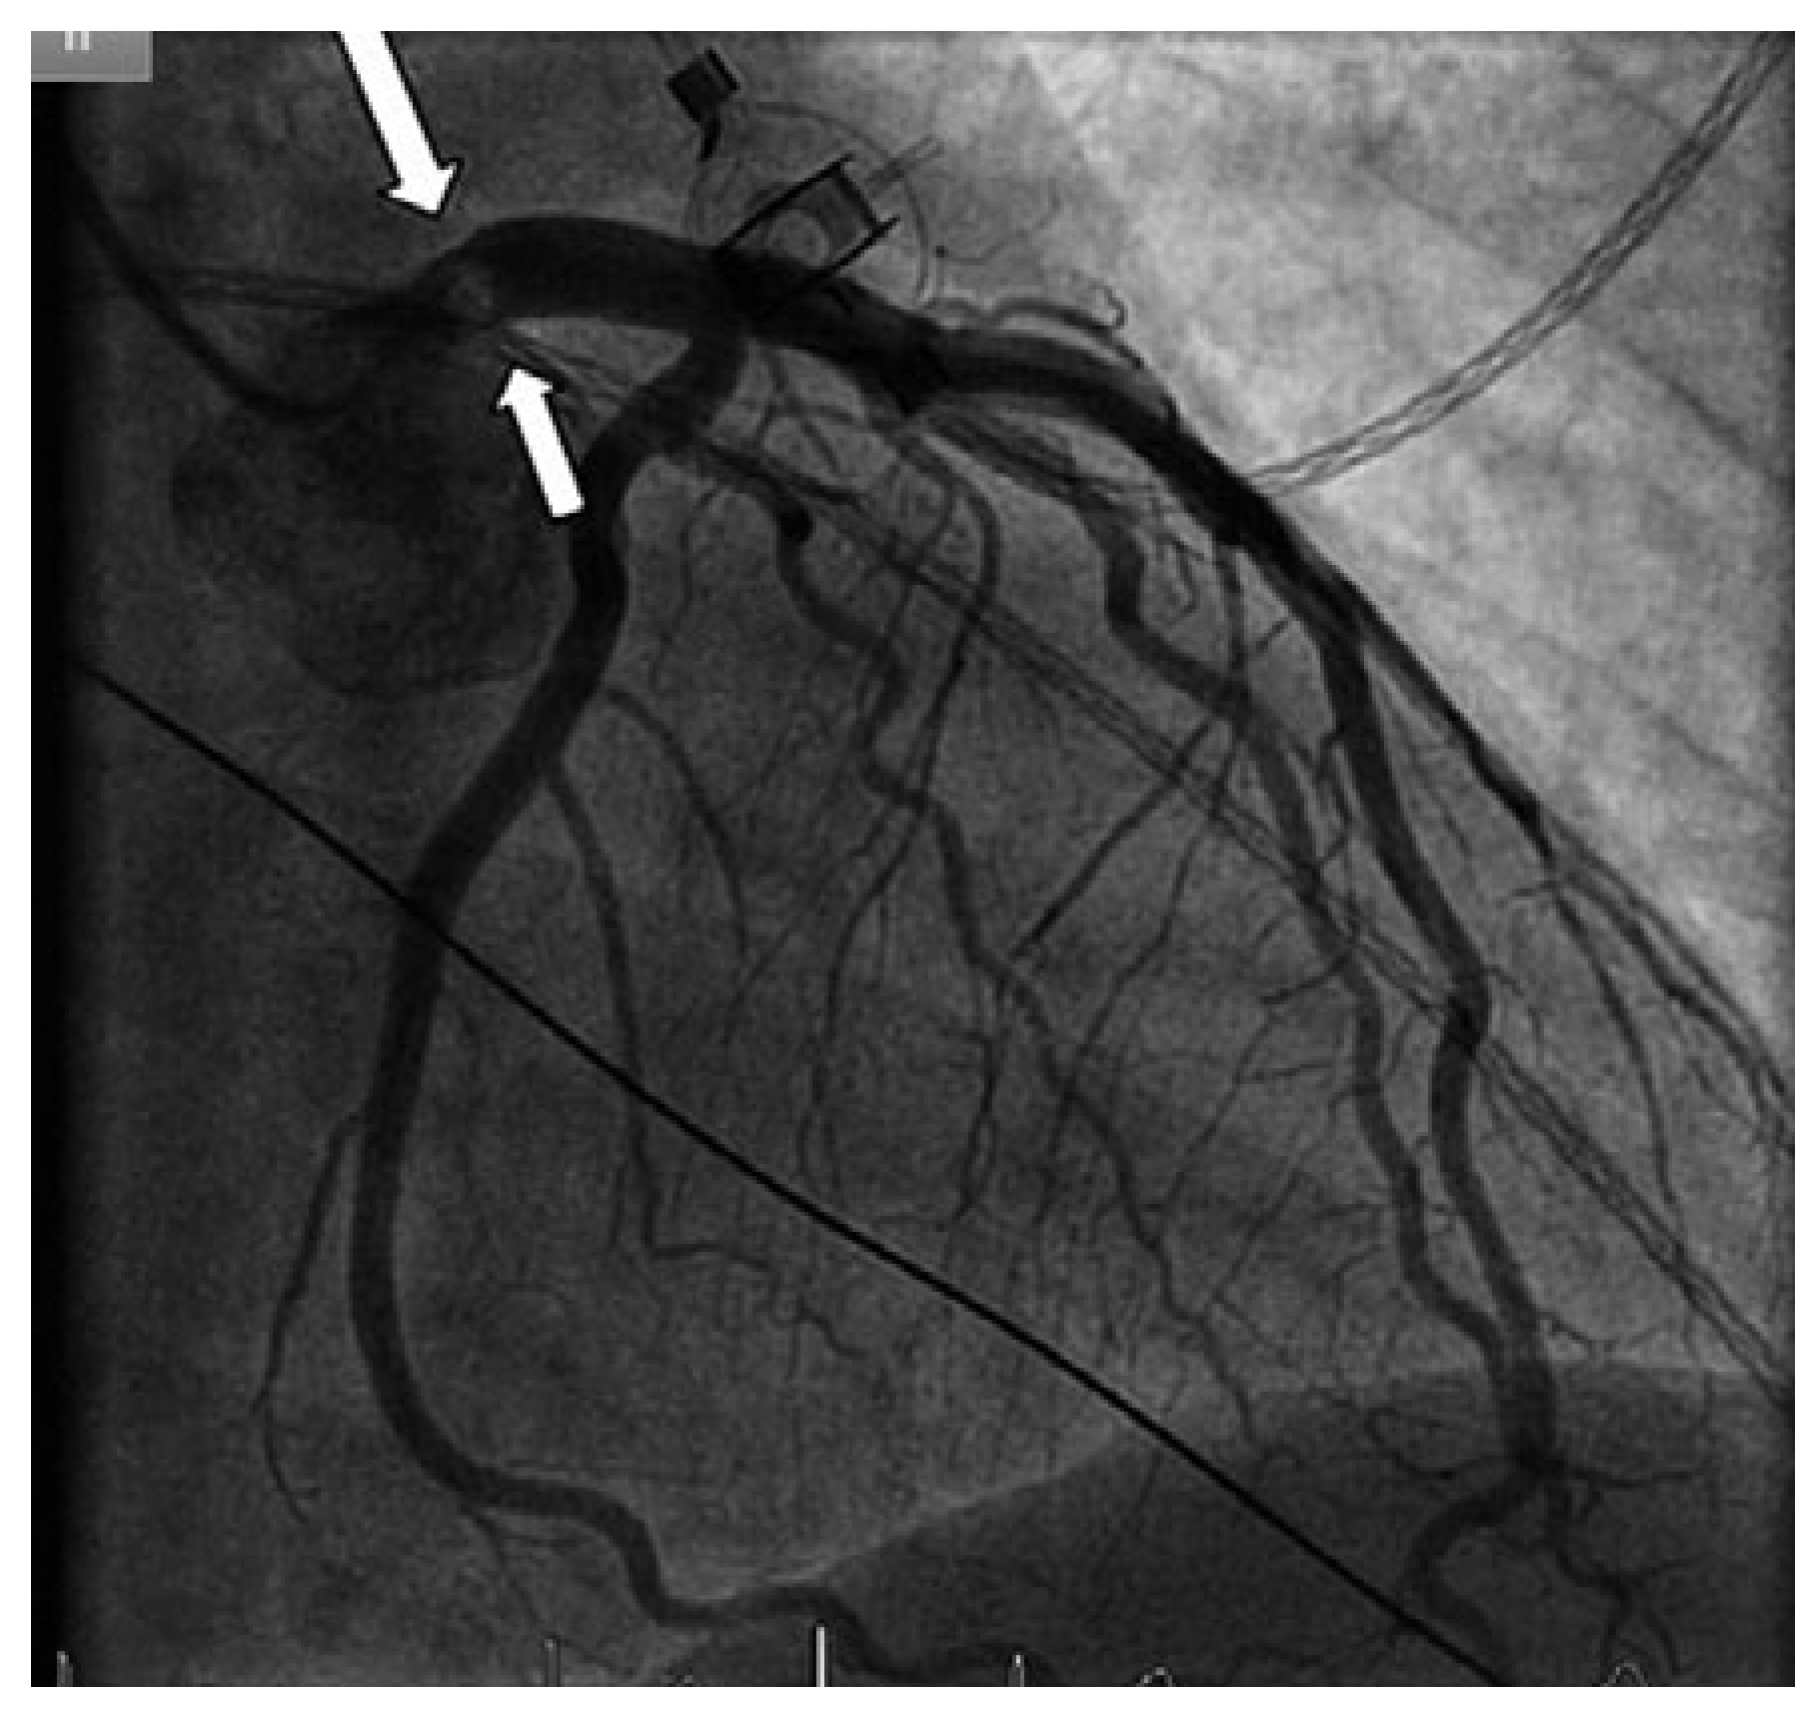

Myocardial Infarction due to Obstruction of the Left Main Coronary

Case report